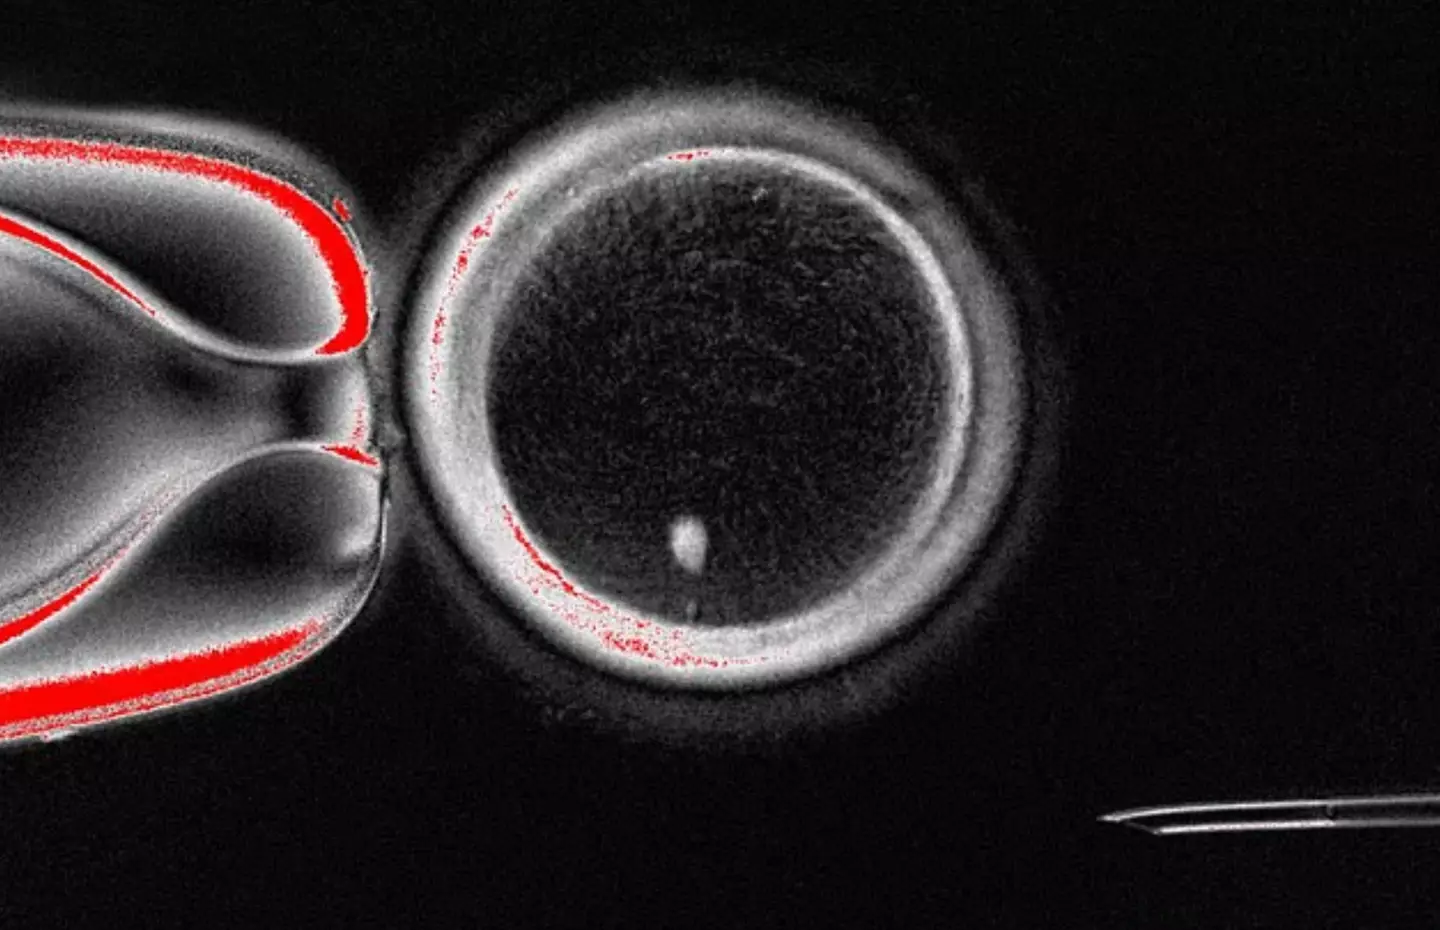

Researchers have succeeded in developing egg-like cells from the DNA of regular skin cells, which have the remarkable potential to undergo fertilization.

This discovery could allow a man’s skin cells to be inserted into a donor egg, followed by fertilization from another male, presenting a genuine possibility of two men conceiving a child without requiring female DNA. However, this development may still be a decade or more away if it ever becomes a reality.

“The ability to generate new eggs would be a major advance. This study shows that the genetic material from skin cells can be used to generate an egg-like cell with the right number of chromosomes to be fertilized and develop into an early embryo.”

According to ScienceAlert, fertility expert Ying Cheong remarked: “For the first time, scientists have shown that DNA from ordinary body cells can be placed into an egg, activated, and made to halve its chromosomes, mimicking the special steps that normally create eggs and sperm.